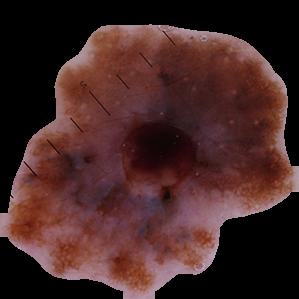

Examples of Malignant Skin Lesions

Source: National Cancer Institute

Melanoma

Asymmetrical Melanoma

Melanoma Advanced Stage

Basal Cell Carcinoma Ulcerated

Basal Cell Carcinoma Superficial

Basal Cell Carcinoma

Kaposi’s Sarcoma

Squamous Cell Carcinoma